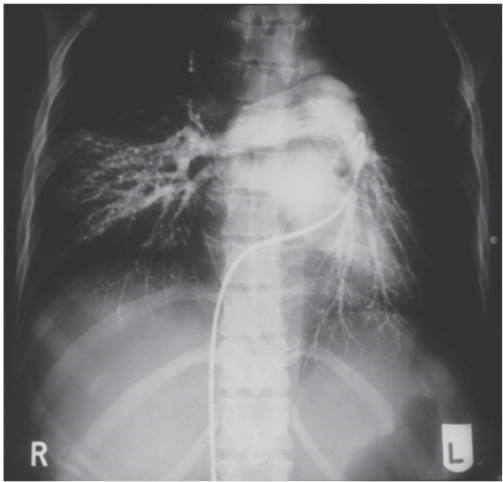

Uma mulher, 32 anos, foi internada devido a uma dispneia intensa e vertigem ao esforço. Durante a anamnese, ela relata parto vaginal cerca de 3 meses antes de buscar o pronto-socorro e retorno recente do uso de anticoncepcionais orais combinados. Apresenta dor torácica bilateral, sugestiva de caráter pleurítico. Foi solicitada uma angiotomografia com o resultado a seguir:

Com isso, o diagnóstico mais provável é: